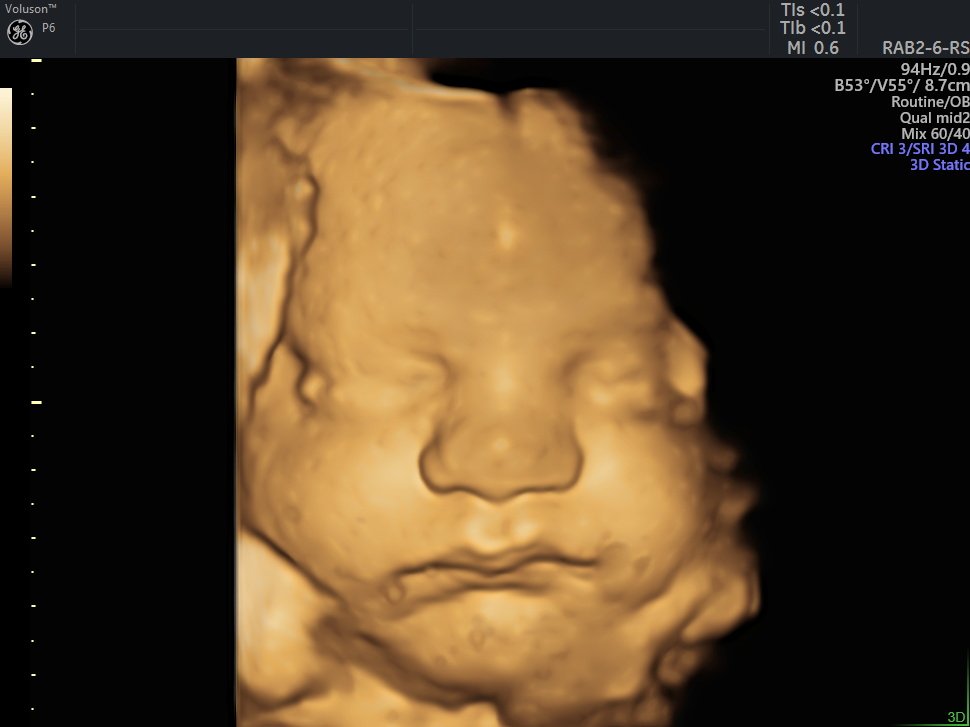

4 Boyutlu (Renkli) Ultrason ve Doppler Ultrasonografi

4 D Ultrasonografi